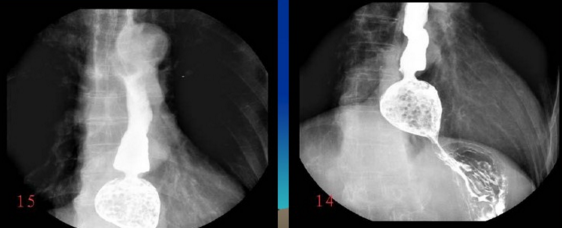

很多人沒有接觸到數字胃腸一體機,可能對它還比較陌生。其實它是一款多功能數字造影胃腸機,功能強大,操作便捷,可以真正實現數字化攝影,以及無膠片化管理,配置先進的工作站,可以保證其圖像畫質。同時它在臨床上的應用也比較的廣泛,能夠檢查多種疾病。下面,由普愛醫療小編詳細列舉一些。

3、氣鋇雙重對比造影。